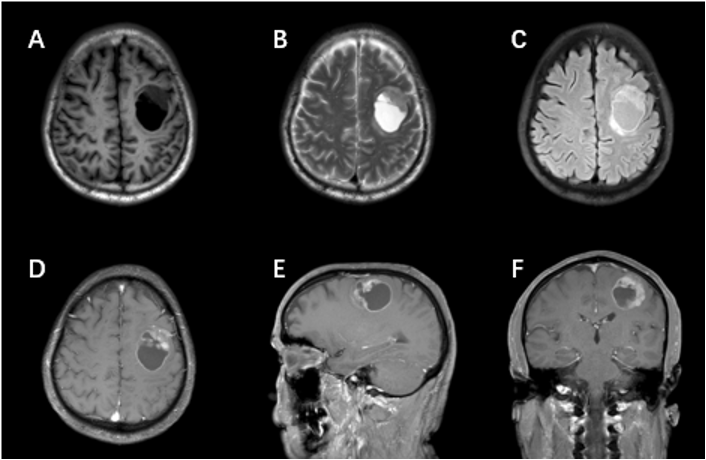

入院后完善常规检查,各项指标未见异常。头颅MRI增强扫描显示:1、左侧额叶见类圆形占位性病变,大小约3.8×3.1×3.2 cm,边界清晰,周围轻度水肿

,增强扫描示实性成分明显强化(图1);2、MRS示病灶侧对比镜像侧Cho/NAA比值显著升高;3、DTI示左侧额顶部皮质脊髓束受压移位伴局部缺损,余白质纤维束走行正常。结合临床表现与影像学特征,初步诊断为:左侧额叶高级别胶质瘤

。

图1.患者术前头颅MRI显示左侧额叶病变部位